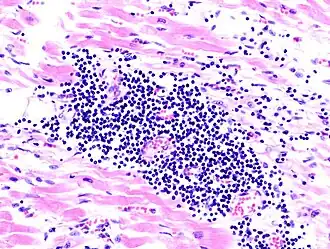

Image anatomopathologique d'une myocardite lors d'une autopsie chez un patient avec une apparition aigüe d'une insuffisance cardiaque congestive

• Biopsie de myocarde : la biopsie objective une infiltration du myocarde par les lymphocytes ou quelquefois par les macrophages, une autre variété de globules blancs. Elle est accompagnée d'autre part d'une multiplication des cellules conjonctives avec parfois nécrose. L'élément clé reste la biopsie du myocarde, faite par voie endovasculaire : un cathéter comportant une pince à son extrémité est introduite dans le ventricule droit par l'intermédiaire de la veine fémorale, sous contrôle radiologique et sous anesthésie locale (biopsie endomyocardique). Elle est réservée aux cas graves avec insuffisance cardiaque d'apparition récente[5]. Elle permet l'isolement et l'identification du virus responsable.